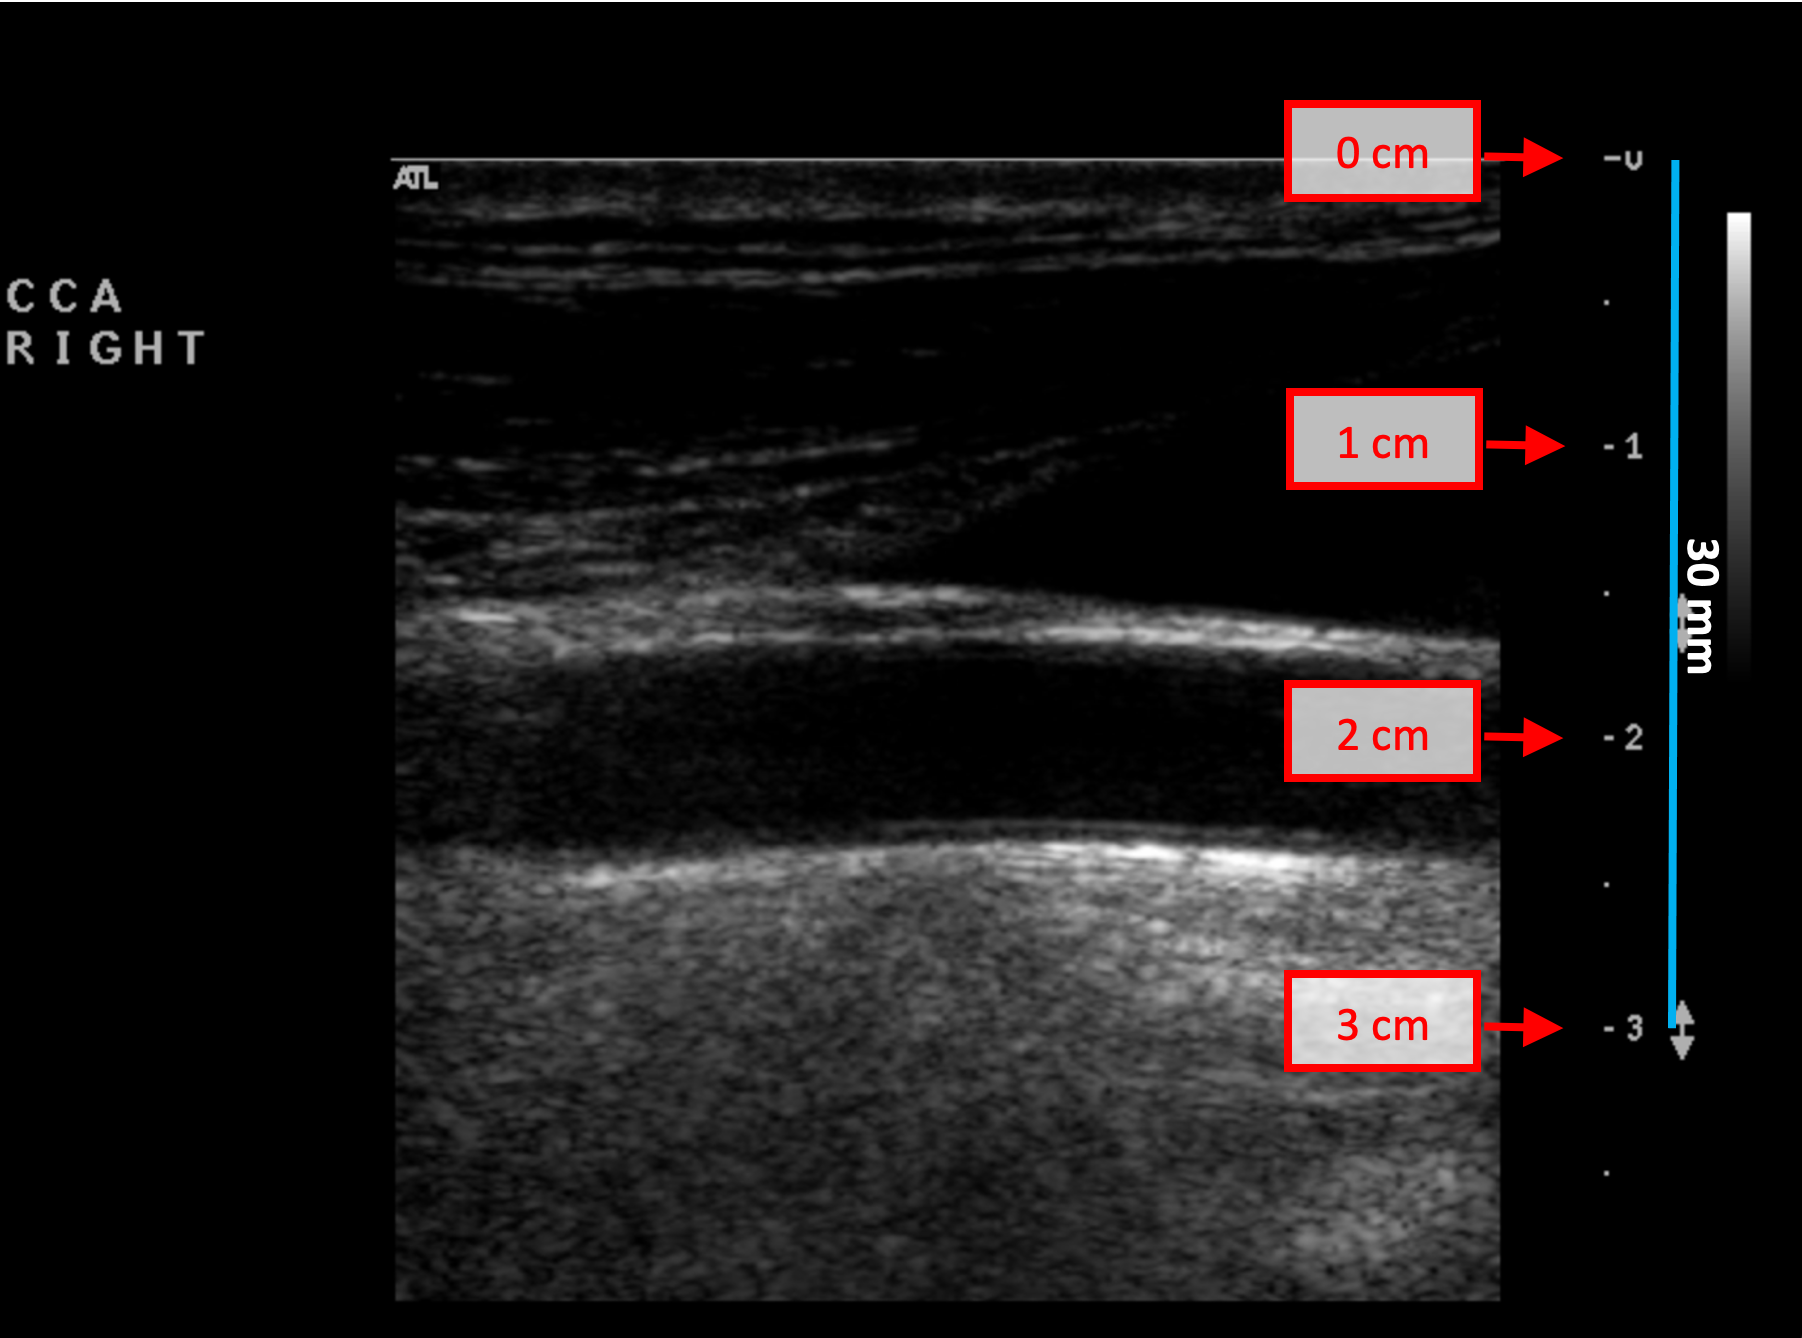

B-mode calibration examples

The following images show examples of calibrations of the b-mode image. Graphic items in red shows where you can find the information about the depth of the image in the ultrasound image.